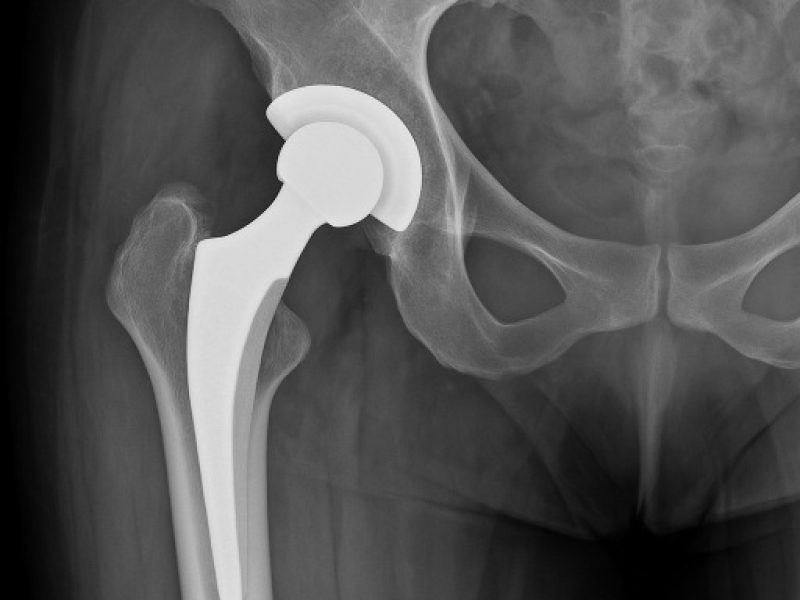

Il dolore all’anca può limitare ogni aspetto della vita quotidiana: camminare, salire le scale, dormire serenamente, praticare attività fisica.La protesi totale di anca rappresenta oggi una soluzione sicura, efficace e definitiva per ritrovare libertà di movimento e qualità di vita.Grazie a tecniche chirurgiche evolute e a un percorso altamente personalizzato, accompagniamo il paziente verso un recupero stabile, rapido e duraturo.

Accesso Laterale e Postero-Laterale

Accesso Laterale

• Elevata stabilità dell’impianto

• Ottimo controllo dell’allineamento protesico

• Sicurezza nel decorso post-operatorio

• Recupero progressivo e controllato

È particolarmente indicata nei pazienti in cui è prioritario massimizzare la stabilità dell’articolazione.

Accesso Postero-Laterale

Tecnica consolidata e ampiamente utilizzata a livello internazionale, offre:

• Eccellente esposizione dell’articolazione

• Precisione nel posizionamento delle componenti

• Rispetto delle strutture muscolari

• Recupero funzionale efficace

La ricostruzione accurata dei tessuti garantisce stabilità e ottime performance nel tempo.